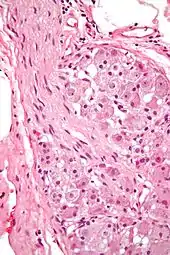

![]() Various forms of nerve cells.

In neurophysiology, a ganglion cell is a cell found in a ganglion (a cluster of neurons in the peripheral nervous system). Examples of ganglion cells include:

- Retinal ganglion cell (RGC) found in the ganglion cell layer of the retina[1]

- Cells that reside in the adrenal medulla, where they are involved in the sympathetic nervous system's release of epinephrine and norepinephrine into the blood stream

- Cells of the sympathetic ganglia

- Cells of the parasympathetic ganglia

- Cells of the spiral ganglia[2]